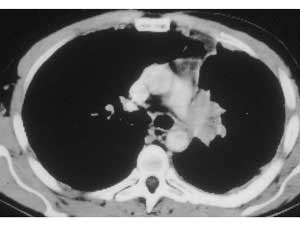

Infiltration of the PA on the right side requiring arterial reconstruction is less frequent. Partial resection of the PA often is performed in conjunction with right upper lobe sleeve resection (Figure 13). After right upper sleeve lobectomy en bloc with partial resection of the PA, the stump of the main bronchus and the PA defect are left open in the field (Figure 14). Harvesting of the pericardium is performed as above, based on the size of the portion of the resected pulmonary artery. Patch reconstruction of the PA is completed as above before reimplantation of the bronchus to reduce the arterial clamping time (Figure 15).